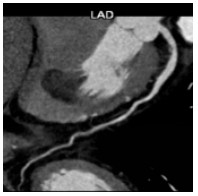

入院后签署患者知情同意告知书,查血常规、凝血谱、电解质、血生化、甲状腺功能、肿瘤标志物、C反应蛋白和脑钠肽均未见明显异常,心电图示窦性心律,顺钟向转位。连续心电遥控监护5 d未见明显室性心律失常。心脏超声和经食道心脏超声检查提示室间隔及左室下壁中段近后内侧乳头肌处可见一个偏高回声区,主要位于心肌内,浸润心肌全层,部分凸向左室腔,略见活动及变形,未累及二尖瓣和主动脉瓣,未见心腔流入道和流出道梗阻,未见明显心包积液。左心声学造影显示室间隔中下段偏强回声团块内未见明显血流信号,乏血供表现。心脏多层螺旋计算机断层扫描(CT)示室间隔内异常密度,测其CT值为-31.3 Hu,提示为脂肪组织密度,增强后病灶未见强化,诊断为脂肪来源肿瘤,脂肪瘤考虑(图 1~2)。心脏磁共振(CMRI)增强扫描示FIESTA序列显示后室间隔-左室下壁见一混杂高信号“小核桃”样大小肿物,T2WI(图 3)上为高信号,Triple IR序列(图 4)上病灶全部为低信号,提示为纯脂肪成分,病变周围可见低信号环,提示为化学位移伪影,病变质地较软,边界尚清楚,电影序列可见病灶柔软摆动,并随心动周期形态改变,局部突入左心室,舒张末期测量大小约25 mm×19 mm×36 mm,灌注序列见灌注确实,延迟增强未见强化,拟诊为心脏脂肪瘤(图 5)。SPECT心肌静息灌注显像见室间隔和左室下壁局部心肌血流灌注减低。18F-FDG PET-CT显像提示室间隔-左室下壁心肌内病变糖代谢减低,考虑为脂肪源性病变,全身未见局部异常密度增高。

| 图 1 心脏CT图(室间隔肿瘤在T2WI像上显示为高信号) |

当发现存在心脏肿瘤时,首先需要明确其性质,尤其是良恶性。CT和磁共振对脂肪瘤的识别具有高度特异性[12-13],本患者CT检查示室间隔脂肪组织均匀低密度影。MR清晰显示肿瘤边界,T1W1呈强信号,T2W1呈稍强信号,脂肪组织序列呈弱信号,钆增强后也未见明显强化,对映证脂肪瘤均有较大价值。患者肿瘤的CT值同皮下脂肪组织,同时结合心超等其他影像学依据可排除黏液样变、血管组织、肌肉组织、纤维组织和错构瘤等其他组织来源,因此可临床确诊为脂肪来源的肿瘤。肿瘤形态、血供是否丰富和代谢是否活跃是鉴别脂肪瘤和脂肪肉瘤的重要依据。超声、CT和磁共振均提示肿瘤为单个,与周围组织边界清楚。患者接受了超声左心声学造影和核素心肌静息灌注显像检查,均提示肿瘤血供明显不丰富。18F-FDG PET-CT检查显示肿瘤放射性摄取呈稀疏缺损区,提示葡萄糖代谢减低,符合良性肿瘤表现,同时也未见全身其余部位有高糖代谢病灶,因此临床诊断良性脂肪瘤成立。2011年AECVP/SCVP心内膜心肌活检共识声明认为对左心系统肿瘤无需进一步进行心肌活检[7]。